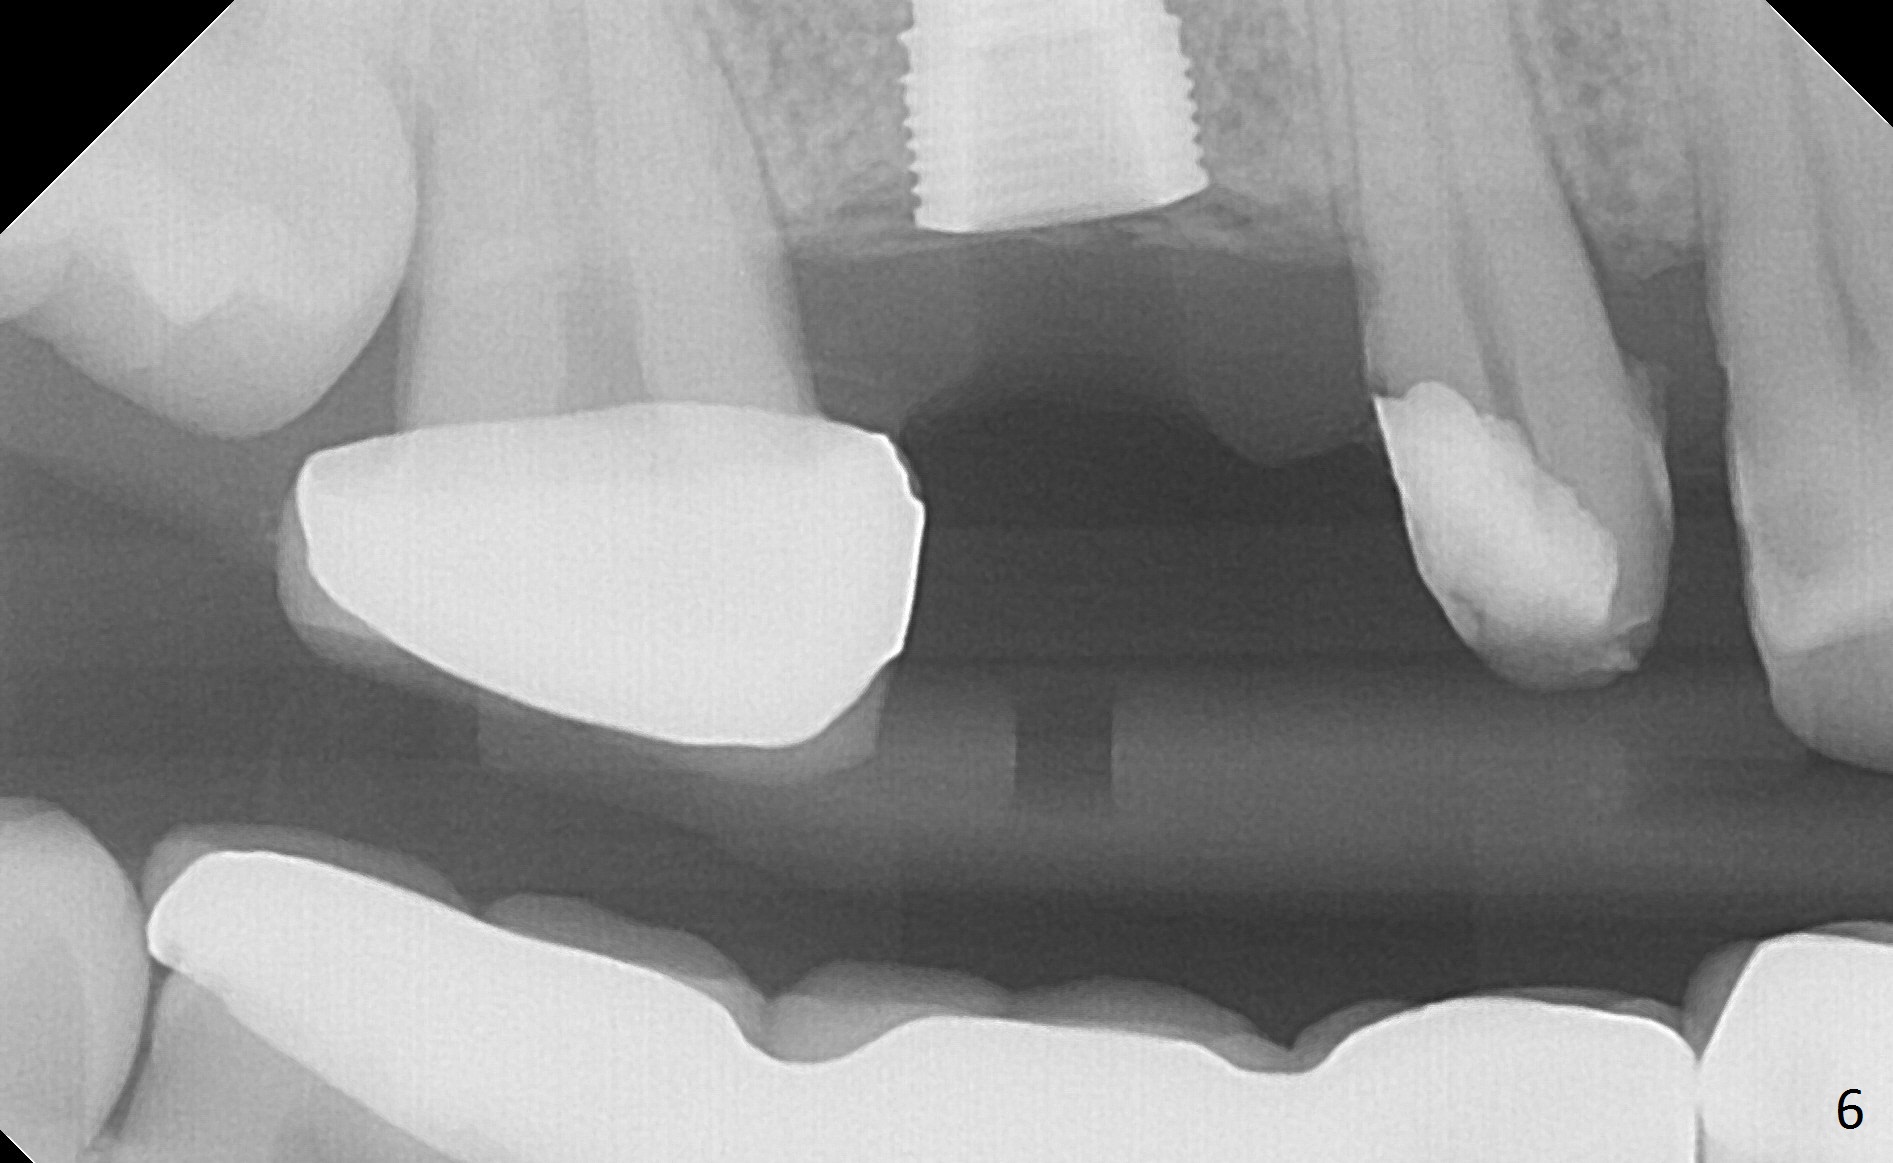

When the bridge is partially removed, the tooth #4 is found to have extensive caries. IRM is placed following carious removal (Fig.1). Magic Split testing shows that the bone density is high (flapless). Osteotomy is initiated by 1.6 mm drill, but the handle of the drill needs to shift mesial (Fig.1 red arrow). When the latter is done, the whole drill (2 mm) needs to move distal (Fig.2 double red arrows). When a 4.5x14 mm drill finishes the osteotomy, it is in the middle of the edentulous space (Fig.3). After use of 5 mm tap, a 5.3x14 mm implant cannot reach the depth (Fig.4,5). Following increase in osteotomy depth from 16 to 18 mm (gingival margin) until 5 mm drill in diameter, the implant placement level is more ideal (Fig.6,7, slightly subcrestal) with insertion torque maintaining at >55 Ncm. The sinus floor (Fig.4 arrowheads) may be penetrated when the osteotomy depth increases (Fig.7 *), but the sinus membrane remains intact.